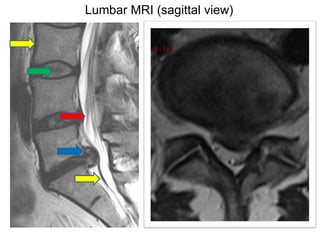

Lumbar MRI (sagittal view)

Lumbar MRI (axial view)

Cauda Equina Syndrome A clinical syndrome due to compression of lumbo-sacral spinal nerves Clinically, radicular pain, uni or bilateral Motor weakness in variable myotomes and sensory loss Perineal numbness Loss of anal tone Loss of bladder function leading to retention Impotence and sexual dysfunction

Complete or incomplete CES Complete CES Objective loss of perineal sensation Bladder retention Patulous anus Incomplete Altered sensation, loss of desire to void and poor stream